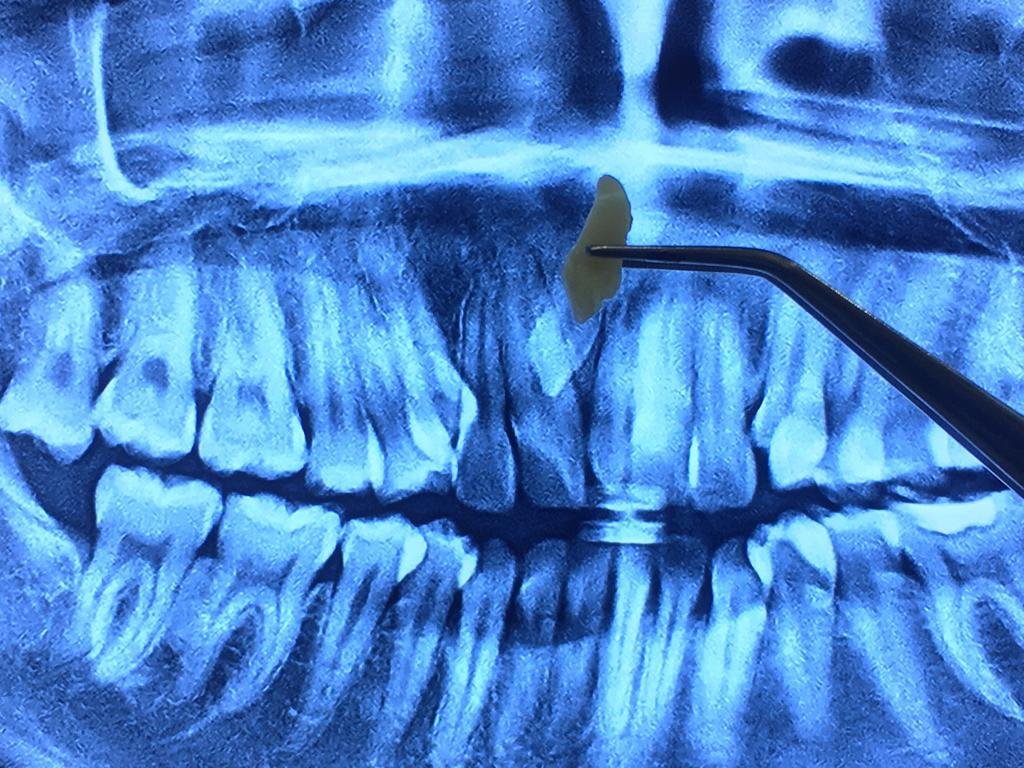

ciri ciri impaksi gigi dan perlu operasi gigi bungsu

Kapan Odontektomi Dibutuhkan?

Pasien biasanya membutuhkan odontektomi dalam kondisi berikut:

• Gigi bungsu impaksi, tumbuh tidak sempurna dan menekan gigi di sebelahnya.

• Infeksi gusi berulang (perikoronitis) karena gigi hanya muncul sebagian.

• Kerusakan gigi sebelahnya akibat dorongan dari gigi bungsu.

• Kista atau tumor rahang yang berkembang di sekitar gigi bungsu.

• Rencana ortodonti (behel) yang mengharuskan dokter menciptakan ruang tambahan pada rahang.

1. Pemeriksaan awal

Dokter melakukan rontgen panoramic untuk melihat posisi gigi bungsu dan menilai kondisi pasien.